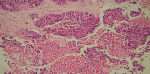

Intervention thérapeutique: devant ce tableau clinique, une intervention chirurgicale par voie combinée a été faite. La voie endonasale a permis l'exérèse de la tumeur par fragmentation, en réalisant une ethmoïdectomie antérieure, postérieure et un accès au sinus frontal. Cependant, la tumeur envahit l'orbite et une voie externe pour un meilleur contrôle de la tumeur a permis la perméabilisation du canal frontal et l'exérèse complète de la tumeur intrafrontale. L'étude histologique de la pièce opératoire a révélé une prolifération carcinomateuse indifférenciée, faite de lobules et de massifs noyés dans un stroma fibreux avec foyer de nécrose (HE x 10) (Figure 4). Les cellules tumorales sont dotées de noyaux atypiques, sans signe de différenciation malpighienne ou glandulaire (HE x 40) (Figure 5). Elles expriment la CKAE1AE3 (Figure 6) et la CK7 (Figure 7). L'INI 1 est retenu. La CK5/6, P63 et la synaptophysine sont négatives.

Figure 4: microphotographie d'un SNUC Une prolifération carcinomateuse indifférenciée, faite de lobule et de massifs noyés dans un stroma fibreux avec foyer de nécrose (HEX10)

Figure 5: cellules tumorales dotées de noyaux atypique, sans signe de différenciation malpighienne ou glandulaire (HEX40)